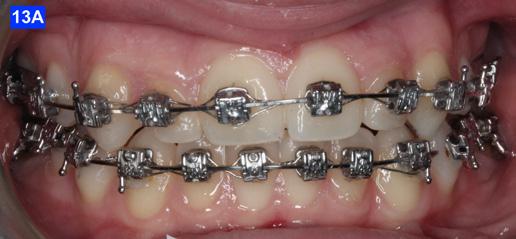

Three months before de-bracketing, while the patient had a .019 x .025 SS arch wire in the maxilla and the mandible, we appointed her for “Count down on retention.” The full arch wire was left in the maxilla, however, in the mandible, it was cut and bent-in, just distally to cuspids. Two triangular elastics were placed per sextant (1/4”– 4.5 oz.) for refinement of the tooth-to-tooth inter-digitation (Figure 13 - A, B, C).8

Figure 13A: Pre-de-bracketing, frontal view

Figure 13B: Pre-de-bracketing, right lateral view

Figure 13C: Pre-de-bracketing, left lateral view